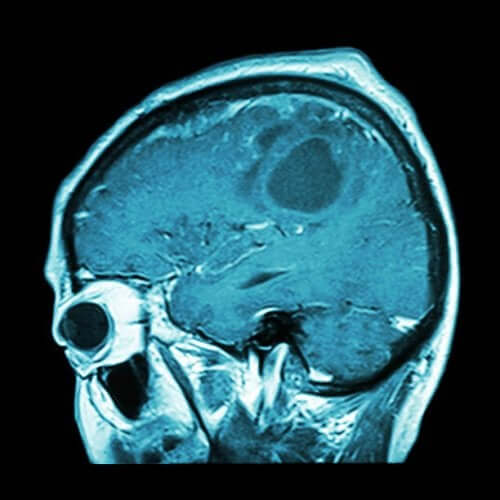

뇌종양 백신이 곧 나올 수 있을까

뇌종양은 가장 공격적인 암 중 하나이다. 하지만 이미 개발된 백신이 뇌종양을 근절할 수 있을지도 모른다. 뇌종양 백신이 곧 나올 수 있을까?

2018년 12월, <엘 파이스>신문은 뇌종양을 앓고 있는 환자를 위한 맞춤형 백신에 대한 기사를 발표했다. 이는 상당히 유망한 결과를 보고한 소수의 참가자를 대상으로 한 연구를 근거로 한다.

하지만 실험 참가자의 수가 적어, 연구원들은 뇌종양에 대한 치료법을 찾았다고 확언하지 못한다. 따라서 증거의 정확성을 확실하게 하고자 추가 연구를 진행해야 한다.

하지만 연구원들은 모든 종양이 정확히 같지 않으며 면역 요법에 모두 잘 반응하지도 않는다는 사실을 발견했다. 따라서 교모세포종을 앓고 있는 환자를 치료하기 위한 ‘정밀 면역 요법’이 연구되었다.

교모세포종은 예후가 가장 나쁜 암 중 하나이다. 따라서 연구 당시 교모세포종 환자들에게는 좋은 결과를 위해 맞춤형 백신이 필요했다. 그렇지만 전문가들은 어떻게 할 수 있을까?

전문가들이 여러 유형의 암과 특히 뇌종양에 대해 이루어 낸 발전은 상당히 유망하다. 하지만 앞서 언급한 연구에 참여한 인원은 30명에 불과하다.

또한 연구에서 뇌종양 환자의 암을 파괴하는 데 실패했다는 점을 짚고 넘어갈 필요가 있다. 그렇지만 환자들이 치료를 받았음에도 사망률이 높은 매우 공격적인 유형의 암에 걸렸다는 점을 중점적으로 알아두는 것이 중요하다.

연구를 통해 달성한 결과는 환자의 기대 수명을 늘리는 것이었다. <엘 파이스> 신문에 나와 있는 기사에 따르면, 뇌종양 환자는 일반적으로 14개월 동안 생존한다. 하지만 백신을 통해 29개월로 늘릴 수 있었다. 두말할 필요 없이, 이는 전문가들이 올바른 방향으로 나아가고 있으며 어쩌면 결정적인 치료법에 가까워졌다는 것을 나타내는 고무적인 숫자이다.